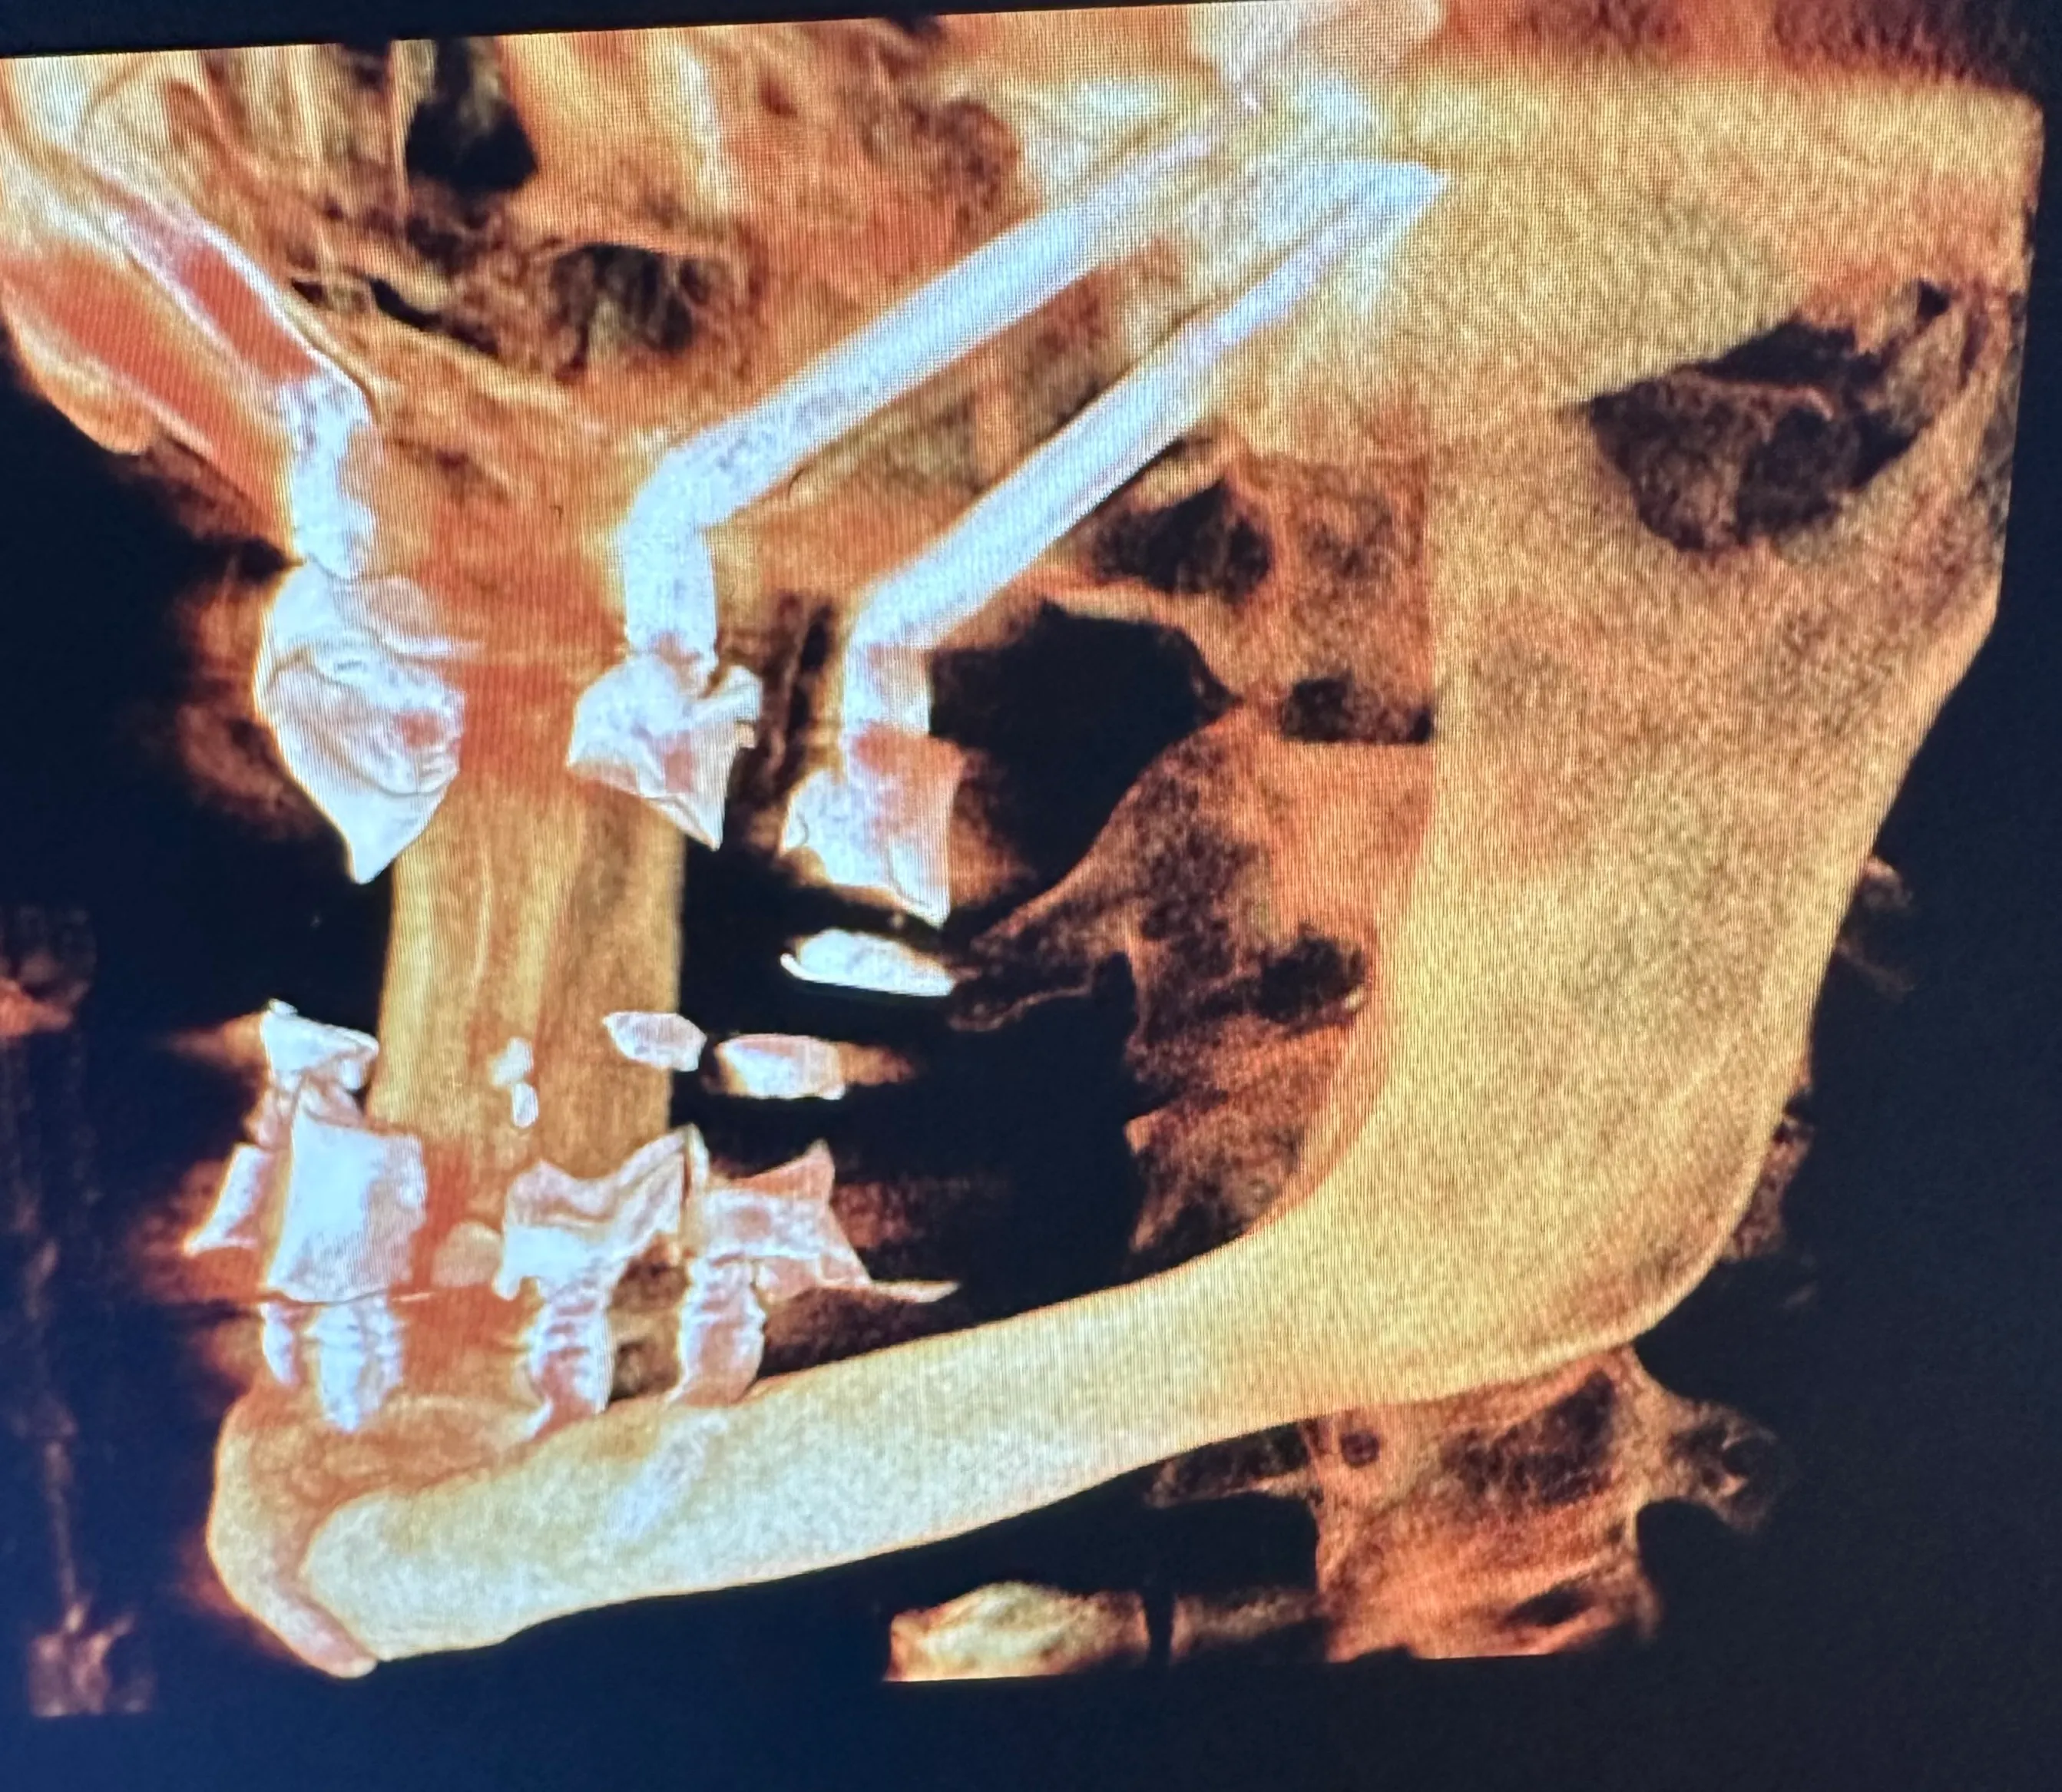

3D illustration of a dental implant with titanium screws in the lower jaw, showcasing gum tissue and natural teeth alignment.

Zygomatic Dental Implants

Some patients need only one or two dental implants, while others are completely edentulous (missing all teeth). As with other well-known implant-supported denture options, zygoma implants can support a full arch of prosthetic teeth on just four screws without bone grafting.

Normally, implants are placed in the maxilla to replace missing teeth in the upper jaw. However, some patients have such severe bone loss that there isn’t enough to place an implant safely. In this case, longer implant screws can be used to reach the cheekbones, which are used as an anchor instead.